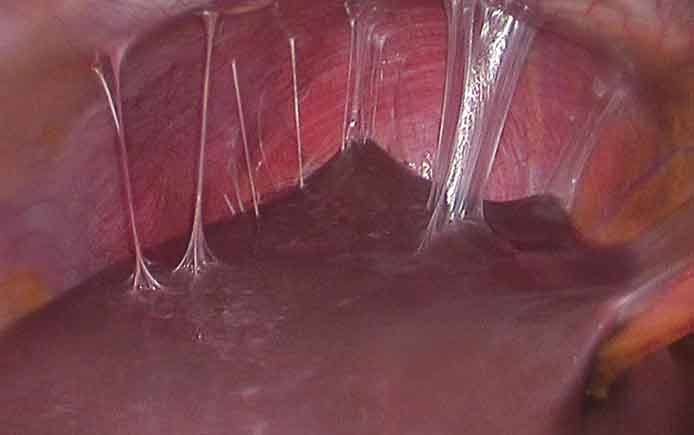

- Гистероскопия. Во время процедуры специальный инструмент (гистероскоп) вводится в полость матки. Так можно визуализировать все происходящее внутри — увидеть спайки, миомы, полипы и т.д. Гистеросальпингография также предоставляет возможность удалить/рассечь образования и таким образом повысить шансы на беременность.

- Лапароскопия. Это метод не только для диагностики, но и лечения спаечной болезни. В ходе операции специальными манипуляторами, помещенным в брюшную полость, врач может проводить какие-то действия (например, рассекать спайки, формировать «заново» маточные трубы и их фимбриальный отдел, выделять из спаек яичники), но и видеть все происходящее на экране.

- гистероскопия — помогает избавиться от синехий в полости матки и цервикальном канале, влагалище;

Успешное лечение спаек в полости матки возможно при проведении хирургического вмешательства. Женщинам с синдромом Ашермана показано проведение гистероскопии. В период подготовки к операции пациентке назначают гормональную терапию. Ее цель – препятствовать росту эндометрия. Во время операции используют различный инструментарий (корпус гистероскопа, эндоскопические ножницы, щипцы, лазер) в зависимости от степени тяжести заболевания.

Во время операции проводят иссечение и удаление спаек. Необходимы меры по защите эндометрия. Для этого используют ультразвуковой контроль. Соблюдение контроля позволяет избежать риска развития кровотечения и перфорации стенок матки. Риск кровотечения возрастает, когда синехии заполняют собой всю полость.